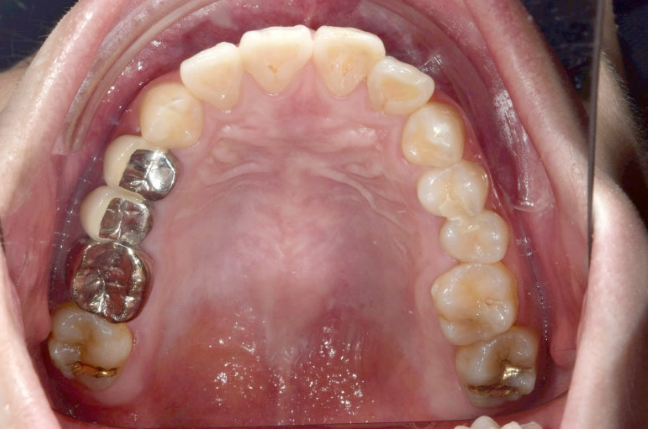

앞니 후방이동량이 큰만큼 앞니에 약간의 치근흡수가 보입니다.

치근평행도는 좋습니다.

어금니 쓰러짐은 인비절라인 발치교정의 가장 큰 난관입니다.

이 부분이 잘 컨트롤 되어야 엑스레이를 찍어봐도 결과가 좋다고 말할 수 있습니다.